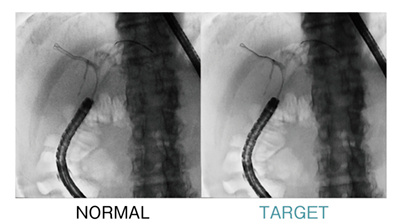

■標的を逃さない。「TARGET」

ガイドワイヤを素早く動かすようなシーンで威力を発揮する低残像な透視画像技術である(図2)。ピクセル単位で動きベクトルを算出する「オプティカルフロー」技術を採用し,透視画像内の局所的な対象物の動きを的確に追従することができる。

図2 TARGET(局所動体追従型残像低減処理)